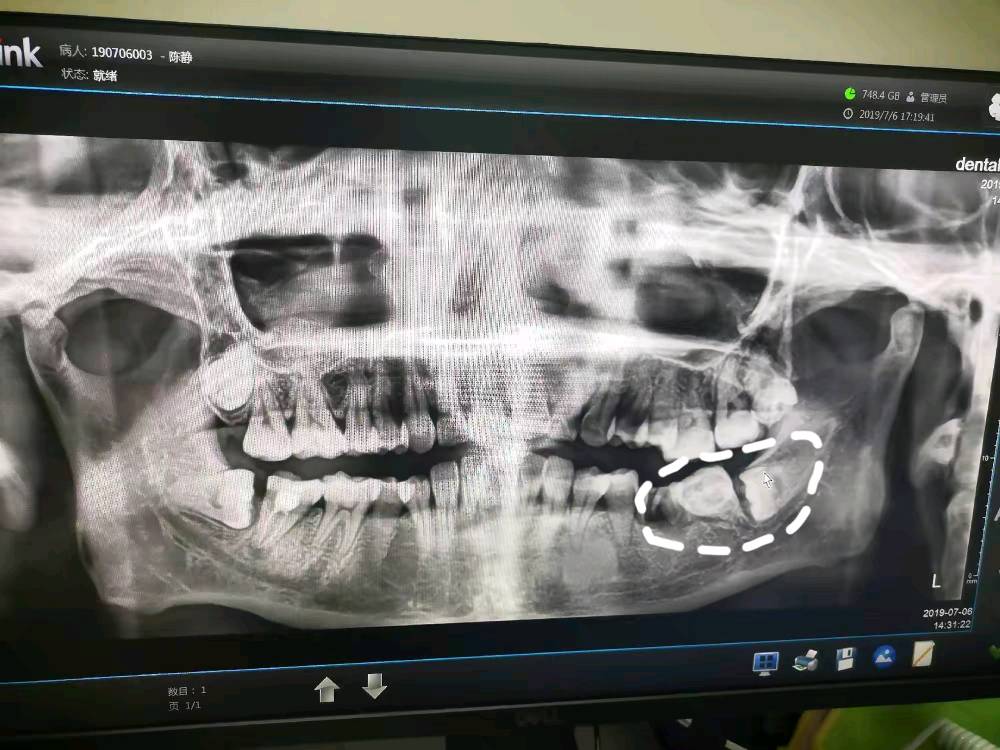

再次展示牙齿长的时候有多聪明,如此的错落,让我刚切开始看到的一点点牙体误以为是第七颗牙,其实人家是倒着的智齿上面的边缘。第七颗牙还在里面的,什么时候眼珠子可以再出来要把它放到患者的口腔里去看看的。

进一步磨除骨质,庐山一角露出来了,那我要怎样开始呢?